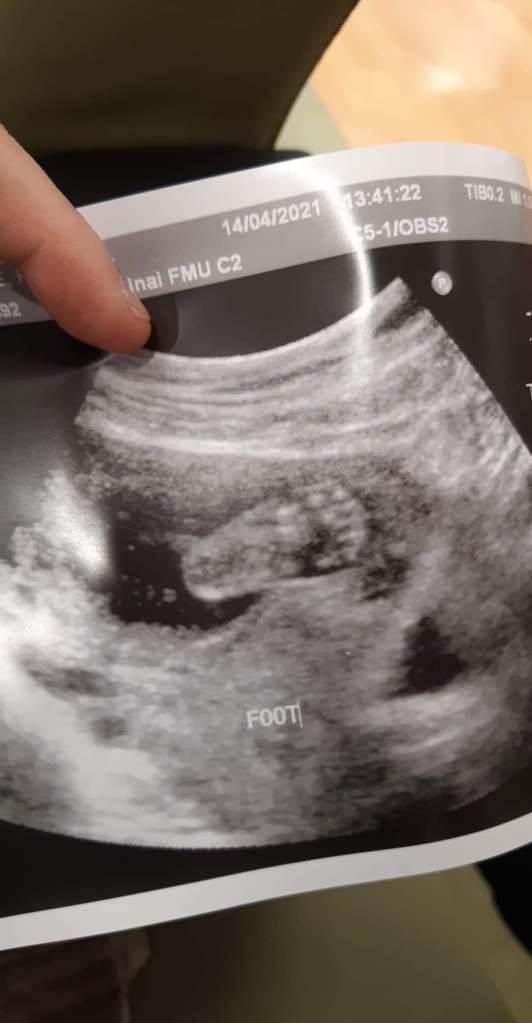

To put into words how this diagnosis has made us feel is truly beyond my capacity. And while this has been of course a sad time, I want it to be clear that sadness is only a piece of this complicated feeling. This baby in some ways has brought us more joy than we thought was possible. To be honest, my brain hasn’t found a way to pinpoint the feelings that fall somewhere between grief, hope, love, challenged, joy, and despair on the spectrum of emotions. We tend to place our emotions into categories, loosely labeled “good” and “bad” ones. Yes, the thought that I will outlive my daughter is devastating and thinking about the physical and intellectual disabilities she will likely have is hard. But I get to hopefully meet another one of my children, marvel in her beauty, and provide her with love, care, and support. She is very alive right now, just ask the inside of Rach’s uterus as she gets daily internal kicks from our little one.

An innate parental need to protect your child at all costs is up against the grim statistical reality. And of course, our daughter is not a statistic, so the intense desire to meet and bond with our new little girl is still burning bright as well. She is still here and growing within Rach, so we want to give her every opportunity to thrive and feel the full volume of our love.